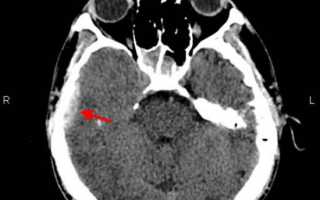

Единственным достоверным методом для выявления эпидуральной гематомы, а также для уточнения её локализации и размера, является компьютерная томография. На КТ головного мозга эпидуральная гематома представляется в виде двояковыпуклой линзы.